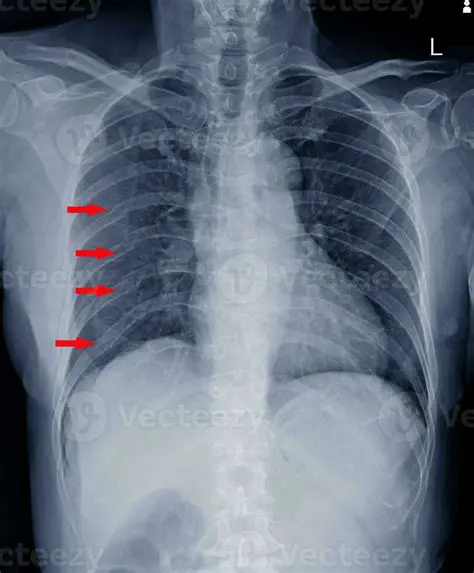

Consequences of Multiple Broken Ribs